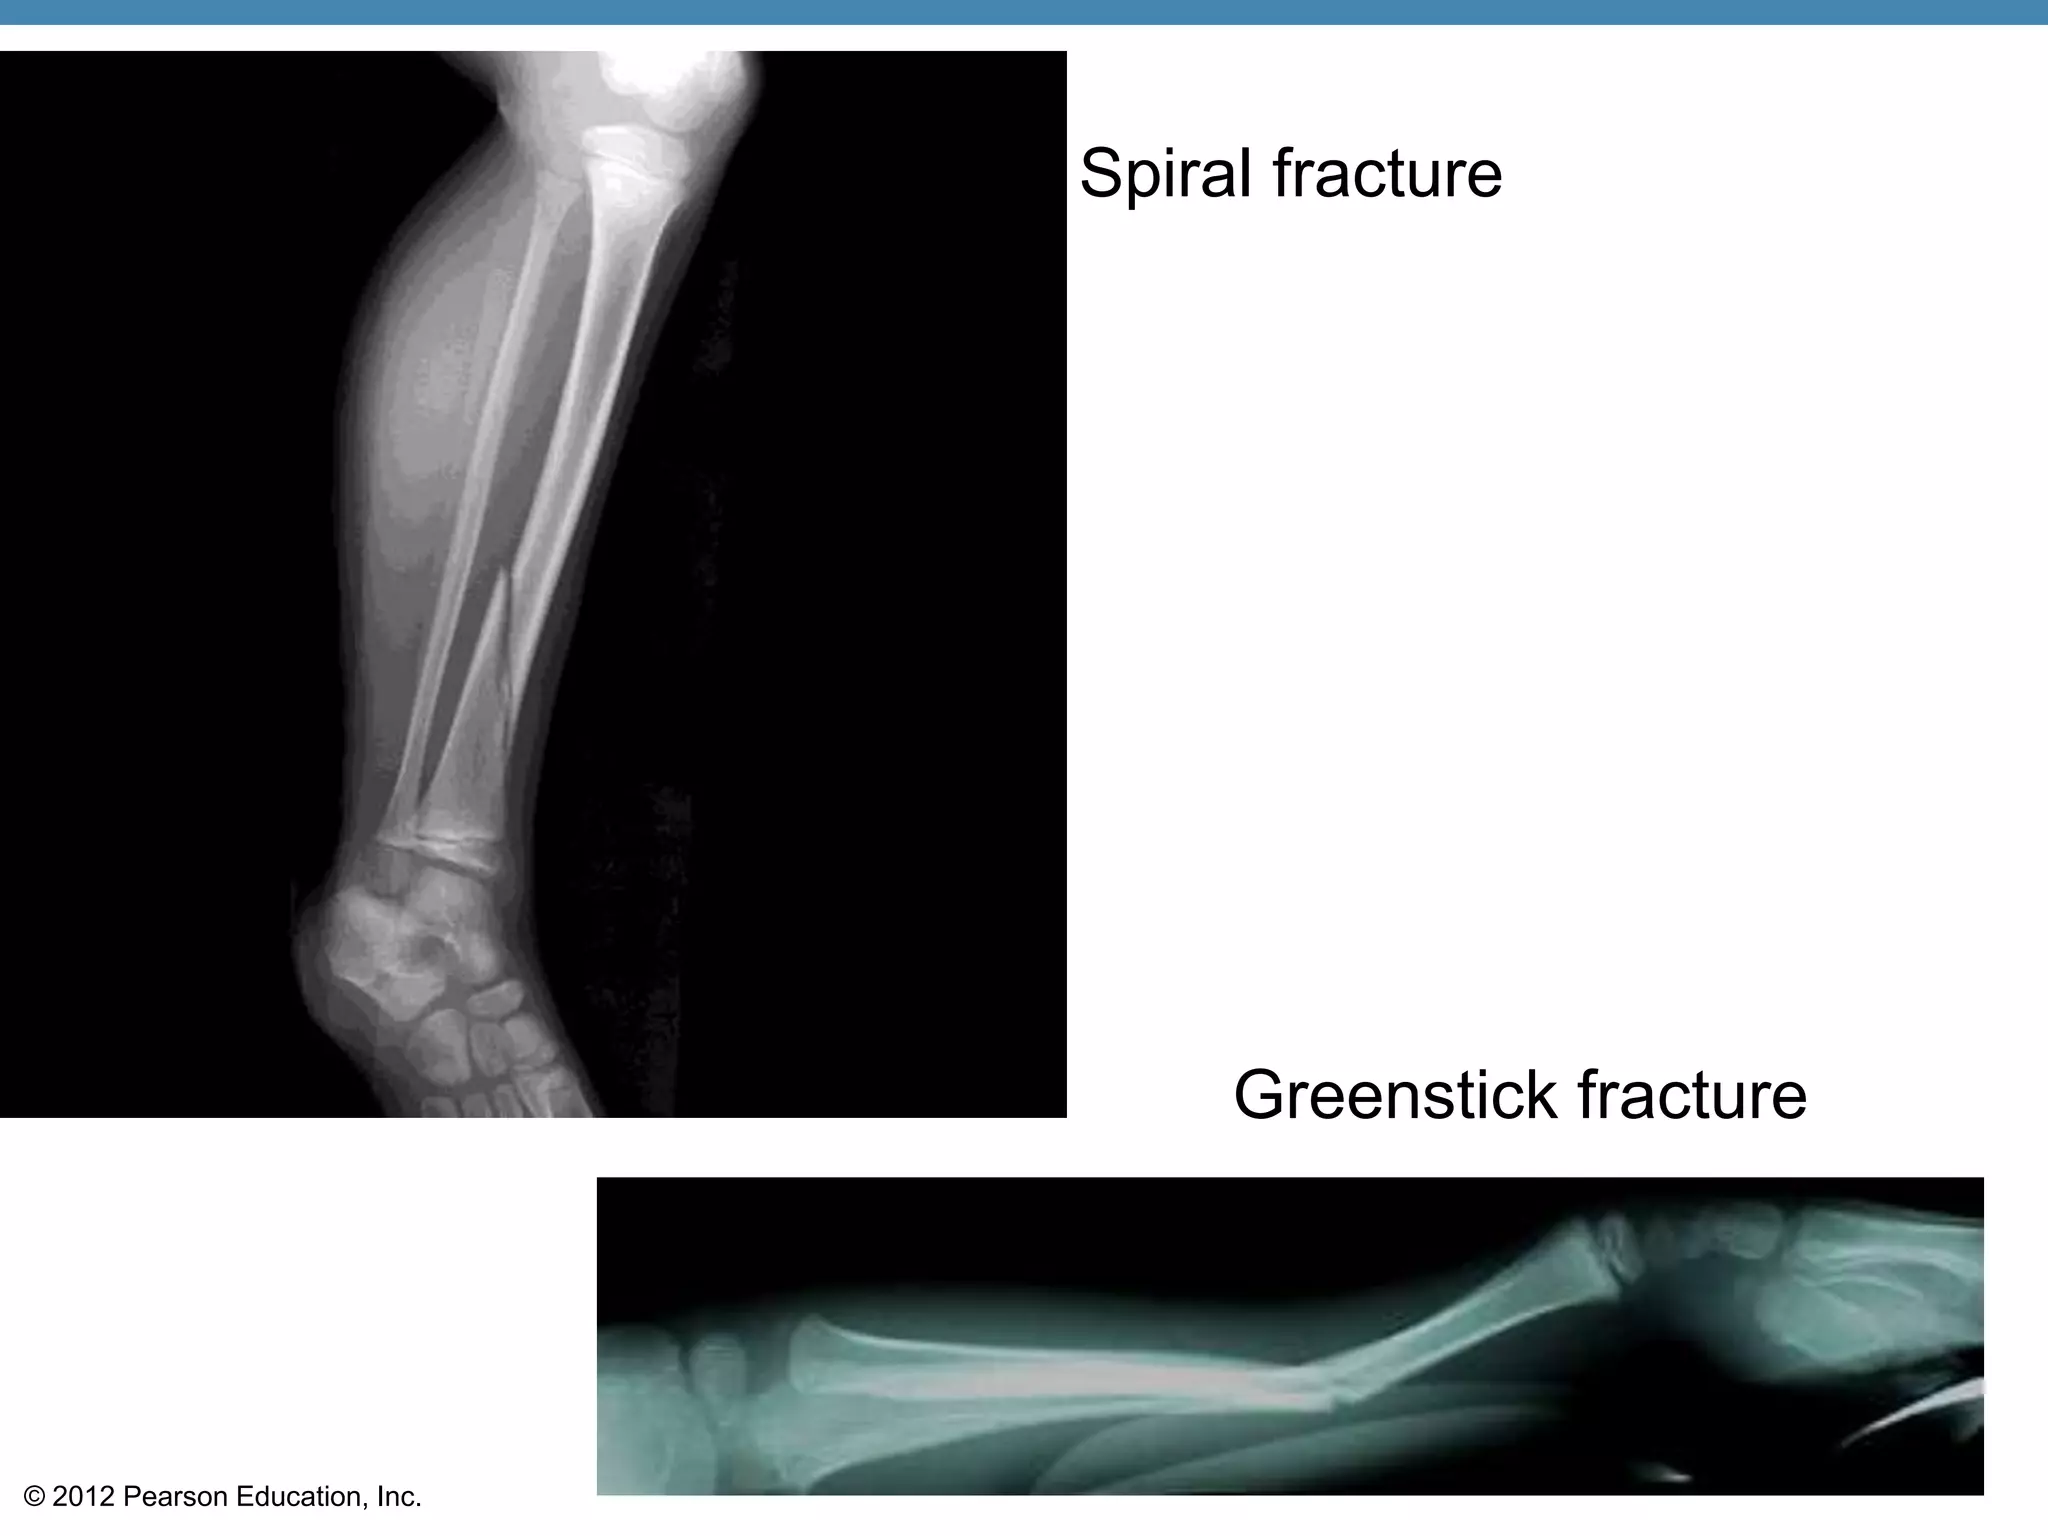

Bone Fractures

•Fracture—break in a bone

•Types of bone fractures

•Closed (simple) fracture—break that does

not penetrate the skin

•Compound fracture—broken bone

penetrates through the skin

•Bone fractures are treated by reduction and

immobilization

Common Types of Fractures

•Spiral—ragged break occurs when excessive

twisting forces are applied to a bone

•Greenstick—bone breaks incompletely

Spiral fracture

Greenstick fracture